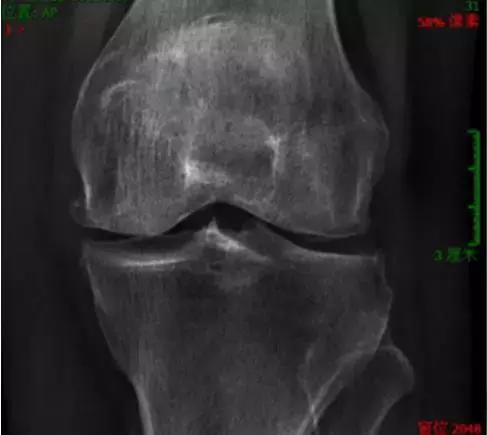

5 骨关节病

久坐或久蹲后起立、上下楼时,关节疼痛明显,休息后缓解。

6 假性痛风

男性患者多,好发于膝关节。发作时肿胀疼痛、皮温高、功能受限。X线片表现半月板、关节软骨面钙化。

骨关节炎又称退行性关节病、增生性关节炎等,一般认为是一种以软骨变性、破坏及骨质增生为特点的关节病,但实际上其也存在关节炎症并可以累及整个关节。膝关节是骨关节炎最常见的发病部位之一。

骨性关节炎是一种退行性病变,可分为原发性和继发性两大类,多见于中老年人,易发在负重较大的膝、髋关节。其病因可能与年龄、肥胖、工作性过度使用等因素有关。60岁以上老年人过半都患有骨关节炎。最常见的症状是早期关节的疼痛。这种疼痛最明显的表现为上下楼梯,特别是下楼梯时膝关节的疼痛。此外比较明显的症状还有晨起时关节僵硬;长期保持一个姿势后,变换姿势时关节活动受限等。